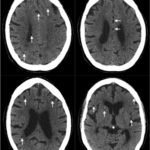

Non-contrast head computed tomography (CT) demonstrates multifocal bilateral hypodense lesions (white arrows) representing air emboli. Note the lesions are located in the intra-axial distribution which indicates an underlying vascular origin.

This event can arise in clinical and non-clinical settings and the diagnosis of cerebral air embolism should begin with clinical suspicion and evaluation. Most common causes include thoracentesis, hemodialysis, angiography, tissue biopsy, scuba diving, and central line or other vascular access procedures. Clinical signs of air embolism are broad depending on the affected system and include altered mental status, focal neurologic deficits in the distribution of the affected neurological region, cyanosis, hypoxia, hypercapnia, hypotension, wheezing, and bronchospasm.4 Recommended diagnostic imaging for cerebral air imaging includes CT and magnetic resonance imaging (MRI), but CT is most often performed first due to availability and the short duration of the test.5 The location of intracranial air emboli can be found in the intra-axial or extra-axial distribution and may indicate the possible etiology. Pneumocephalus is usually found in the extra-axial space most commonly after trauma or neurosurgery while air emboli are found in the intra-axial vascular distribution.6